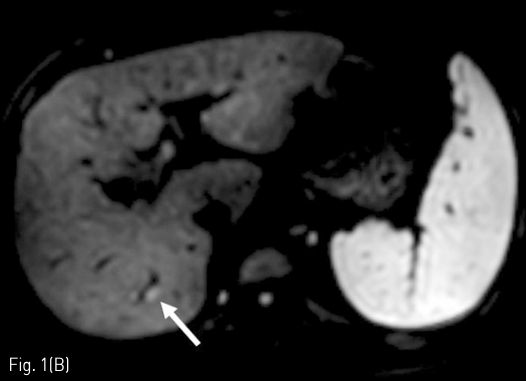

Massive arterioportal shunt after RFA. (A-B) A 1cm-sized tumor (arrow) was identified as low signal intensity on the hepatobiliary phase and high signal intensity on diffusion weighted imaging in the S7 of the liver.

Fig 1B

정기적 추적검사로 시행한 자기공명영상 (MRI)에서 7번 간분절(S7)에 간담도기에 저신호강도로 보이고 확산강조영상에서 고신호강도로 보이는 간암으로 의심되는 결절이 발견되어 고주파 열치료술이 시행되었다 (Fig. 1A, 1B). 10개월 후 추적검사로 시행한 전산화 단층 촬영의 동맥기 영상에서 우측 후방 간문맥이 주위 간동맥만큼 조영증강이 되는 소견을 보이고 있다(Fig. 1C, 1D). 동맥기 영상에서 간동맥과 간문맥 사이에 연결성이 보여 간동문맥단락이 의심되는 소견을 보이고 있다(Fig. 2).